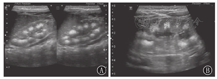

MSK是一种以肾锥体部的集合管弥散性扩张为主要特征的先天性肾髓质囊性病变,其实质是小管扩张,而非真正囊肿性疾病。1939年Lenarduzzi首次对MSK进行了描述[20]。该病无家族史,发病率为1/20 000~1/5 000,可以独立存在,也可以是某个先天综合征的一部分,以肾脏集合管弥散性扩张为特点[21]。但多数患者无症状,实验室检查正常。儿童期起病者少见,临床表现无特异性,多由行腹部超声检查时偶然发现[22,23]。该病双侧发生多见,病变与ARPKD不同,ARPKD随着病情的进展,可同时累及皮髓质,而MSK仅局限于髓质锥体部。肉眼可见肾髓质区多发微小空洞,肾锥体集合管呈线性扇状排列,外观似海绵样,故称海绵肾。由于肾乳头先天性发育异常,其进入肾小盏部位类似括约肌的结构肥厚、收缩,导致乳头管和集合管梗阻而出现囊状扩张、迂曲,产生囊性空腔[24],多数直径为1~3 mm,扩张的囊腔内可充满钙盐,形成砂粒样细小结石。本病超声影像学特点为常累及双侧肾脏,肾脏正常大小或稍大。单个肾锥体呈放射状分布的高回声区,各锥体间呈花瓣样排列,这是由于扩张的集合管囊腔较小,管壁形成大量的反射界面,同时内部伴成簇成团的小结石所致(图4)。肾皮质回声均匀,较正常略薄。本病需与多种原因引起的肾钙质沉着症鉴别。肾钙质沉着症为多种原因引起的肾锥体内钙盐沉积,多见于高血钙症,在原发性肾小管酸中毒、甲状旁腺功能亢进和慢性肾盂肾炎等疾病时最常见,鉴别时需结合临床特点[25]。